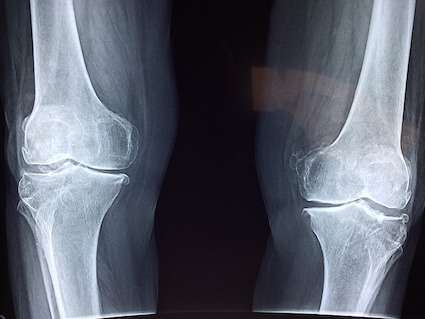

There are many different causes of joint pain including injuries, illnesses, and chronic conditions such as arthritis. Sometimes joint pain can be unpleasant or uncomfortable, and sometimes it can be debilitating. Joint pain is one of the leading causes of disability in the United States. The Centers for Disease Control and Prevention state that nearly one-fourth of adults in the U.S. have arthritis. Many who suffer from joint pain want to treat joint pain naturally instead of relying on pharmaceutical drugs. Pulsed electromagnetic field therapy offers a safe and effective way to treat joint pain naturally.

The specific cause of pain in and around your joints varies. Injuries, exercise, and overuse are just a few of the things that can cause joint pain. Sometimes joint pain occurs when your body identifies a threat that isn't actually there. The tenderness, swelling, and inflammation that we associate with joint pain actually results from the body trying to protect or heal itself. Our body's immune response is triggered whenever our body identifies a threat. If the body detects antigens, it attempts to remove or destroy the substance. Acute joint pain from swelling and inflammation after an injury or exercise is part of your body's natural healing process. However, chronic joint pain from conditions such as arthritis do not typically go away. Managing these symptoms requires treatment.